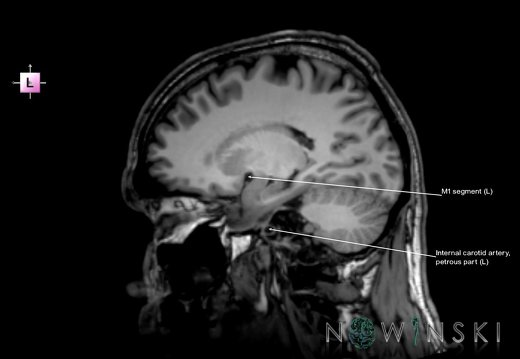

G6.T15.2.V2.P20.Intracranial arteries–Triplanar

G6.T15.2.V2.P20S.Intracranial arteries–Triplanar